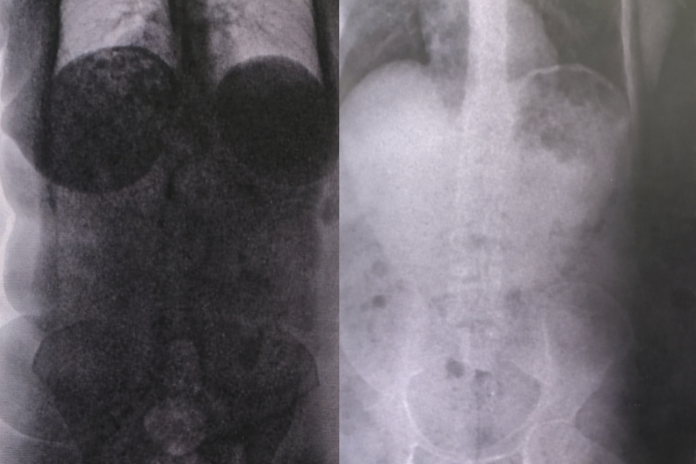

As drogas foram encontradas no estômago dos acusados.

Os dois foram descobertos em momentos distintos durante o procedimento de revista através do raio-X.